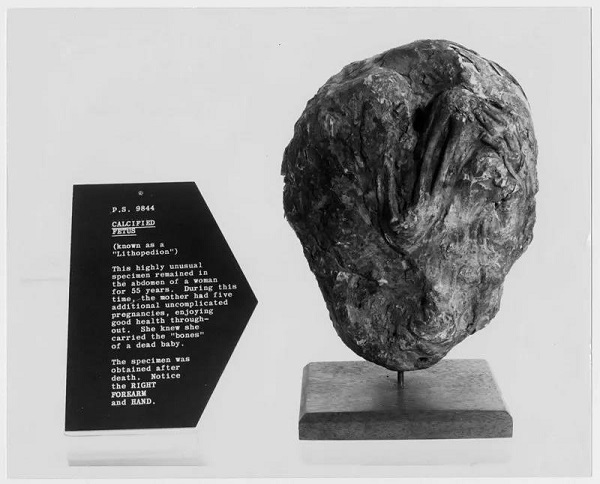

石胎(lithopedion,stone babies), 一种非常罕见的妊娠,是腹腔妊娠的一种结局,而腹腔妊娠属于异位妊娠,发生率为 0.0054%,石胎占其中的 1.3%~2%。腹腔妊娠时,胚胎多在 3 月后死亡,胎儿软组织自动溶解,骨骼难以被吸收,形成钙盐沉着,即形成石胎。

Albucasis 首先报道了石胎,至今文献报道大约有 330 例,发病年龄在 20~100 岁之间,2/3 的患者为 40 岁以上,多见于经济困难和长期不做体检的女性。

胎儿在腹腔内死亡后,母亲的妊娠现象就会自动消失,月经恢复来潮,可无任何不适症状,故死亡的胎儿可长期存留腹腔,文献报道石胎在腹腔的停留时间范围为 4~65 年。

石胎的形成需要特定条件:胎儿至少存活 3 个月后死亡,并保持无菌状态,未被医学检查发现。

文献报道中,胎儿死亡发生在 3~6 月的占 20%,在 7~8 月的占 27%,足月的占 43%。

2016 年土耳其报道了一例 87 岁老年女性死亡后在腹腔内发现的石胎,胎儿尺寸为 12.5×8×5 cm,估计孕周为 25~29 周之间; 同年,Am J Obstet Gynecol 也发表了一篇石胎的报道,估计为孕 13 周。